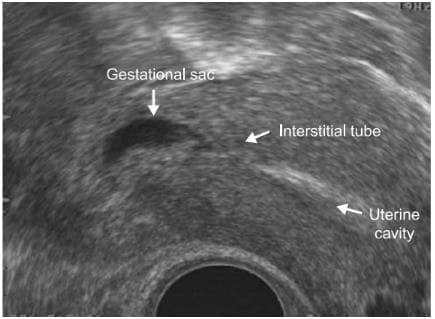

- The implantation of the conceptus in the proximal portion of the Fallopian tube, which is within the muscular wall of the uterus, is called an interstitial pregnancy.

- Interstitial pregnancy remains the most difficult type of ectopic pregnancy to diagnose pre-operatively. This is partly due to lack of any symptoms prior to sudden rupture. In modern clinical practice the diagnosis of inter-stitial pregnancy should be made non-invasively using transvaginal ultrasound.

- The diagnosis is based on the visualization of the interstitial tube adjoining the lateral aspect of the uterine cavity and the gestational sac, the presence of a continuous myometrial layer surrounding the chorionic sac [45] .

An angled view through the uterus revealing an empty uterine cavity and the interstitial segment of the tube adjacent to an ectopic sac. The sac is entirely enclosed by a myometrial layer, which is characteristic of an interstitial pregnancy.